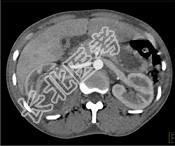

- 单项选择题一女性患者,一月前出现尿频、尿急等症状为引起注意, 现有高热,阅图后最可能的诊断为 ( )

A、急性肾盂肾炎

B、肾脓肿

C、多囊肾

D、肾结核

E、肾癌